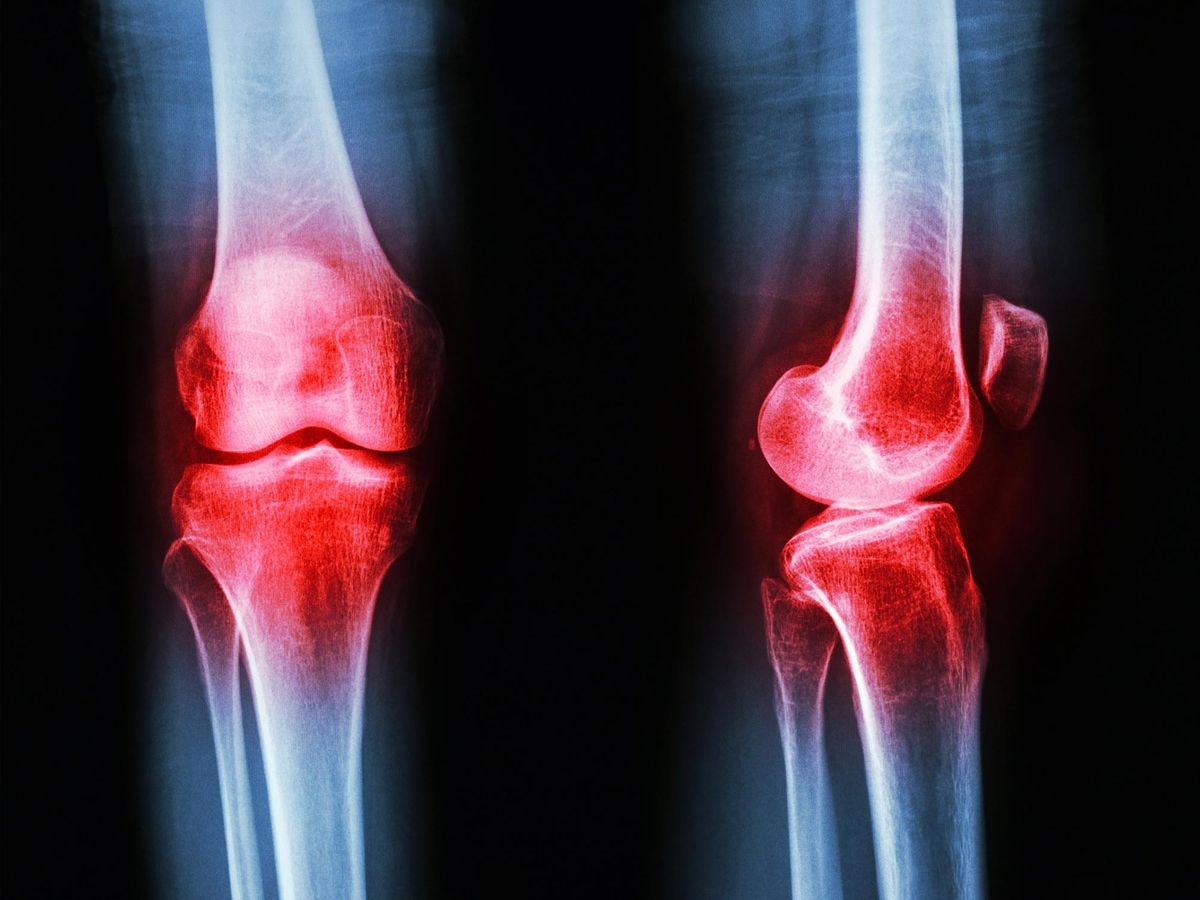

Este avance representa una alternativa prometedora para millones de personas. La osteoartritis afecta a una de cada cuatro personas mayores de 40 años y causa una discapacidad progresiva que limita la calidad de vida.

Las resonancias magnéticas revelaron datos aún más alentadores. Los participantes del grupo de intervención mostraron una degradación más lenta del cartílago en sus rodillas. Este descubrimiento sugiere que la técnica no sólo alivia el dolor actual sino que protege las articulaciones a largo plazo.